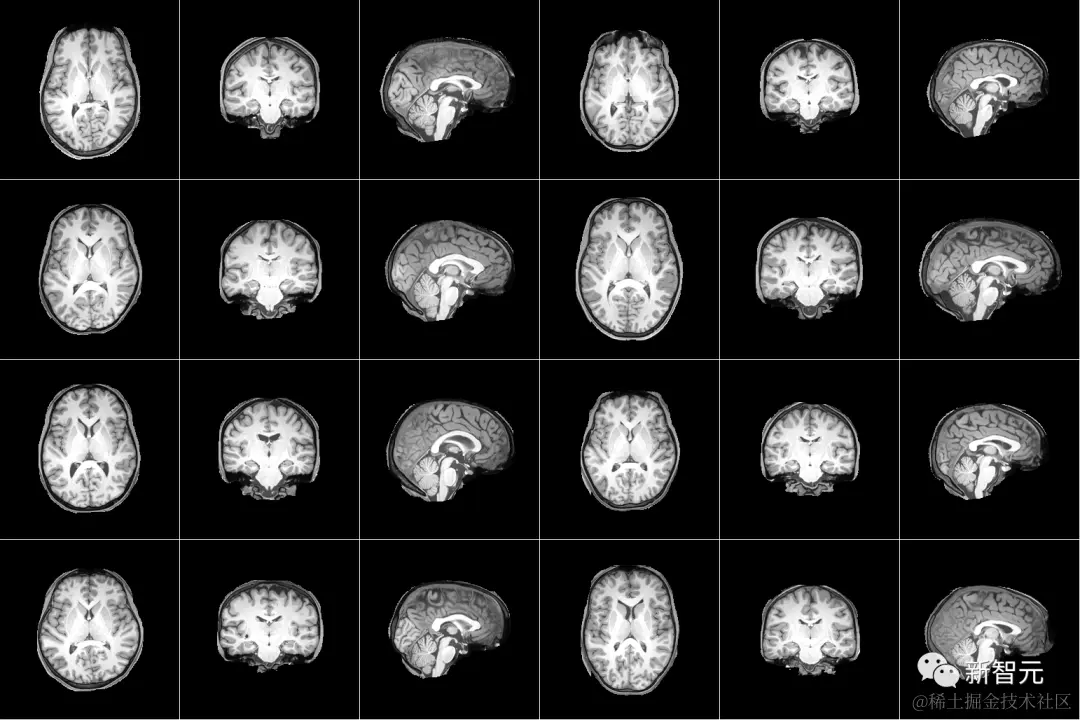

从 MEG 信号中生成图像

虽然将解码作为检索任务会产生很好的结果,但它要求正样本图像必须在检索集中,这在实践中的应用很有限。为了解决这个问题,作者训练了三个不同的大脑模块来预测。

根据表格 1 中的评估指标,生成的图像在视觉上表现出相对较高的质量,多个生成的图像正确地呈现了语义类别。然而,这些生成的图像似乎包含来真实图像的低级视觉信息。